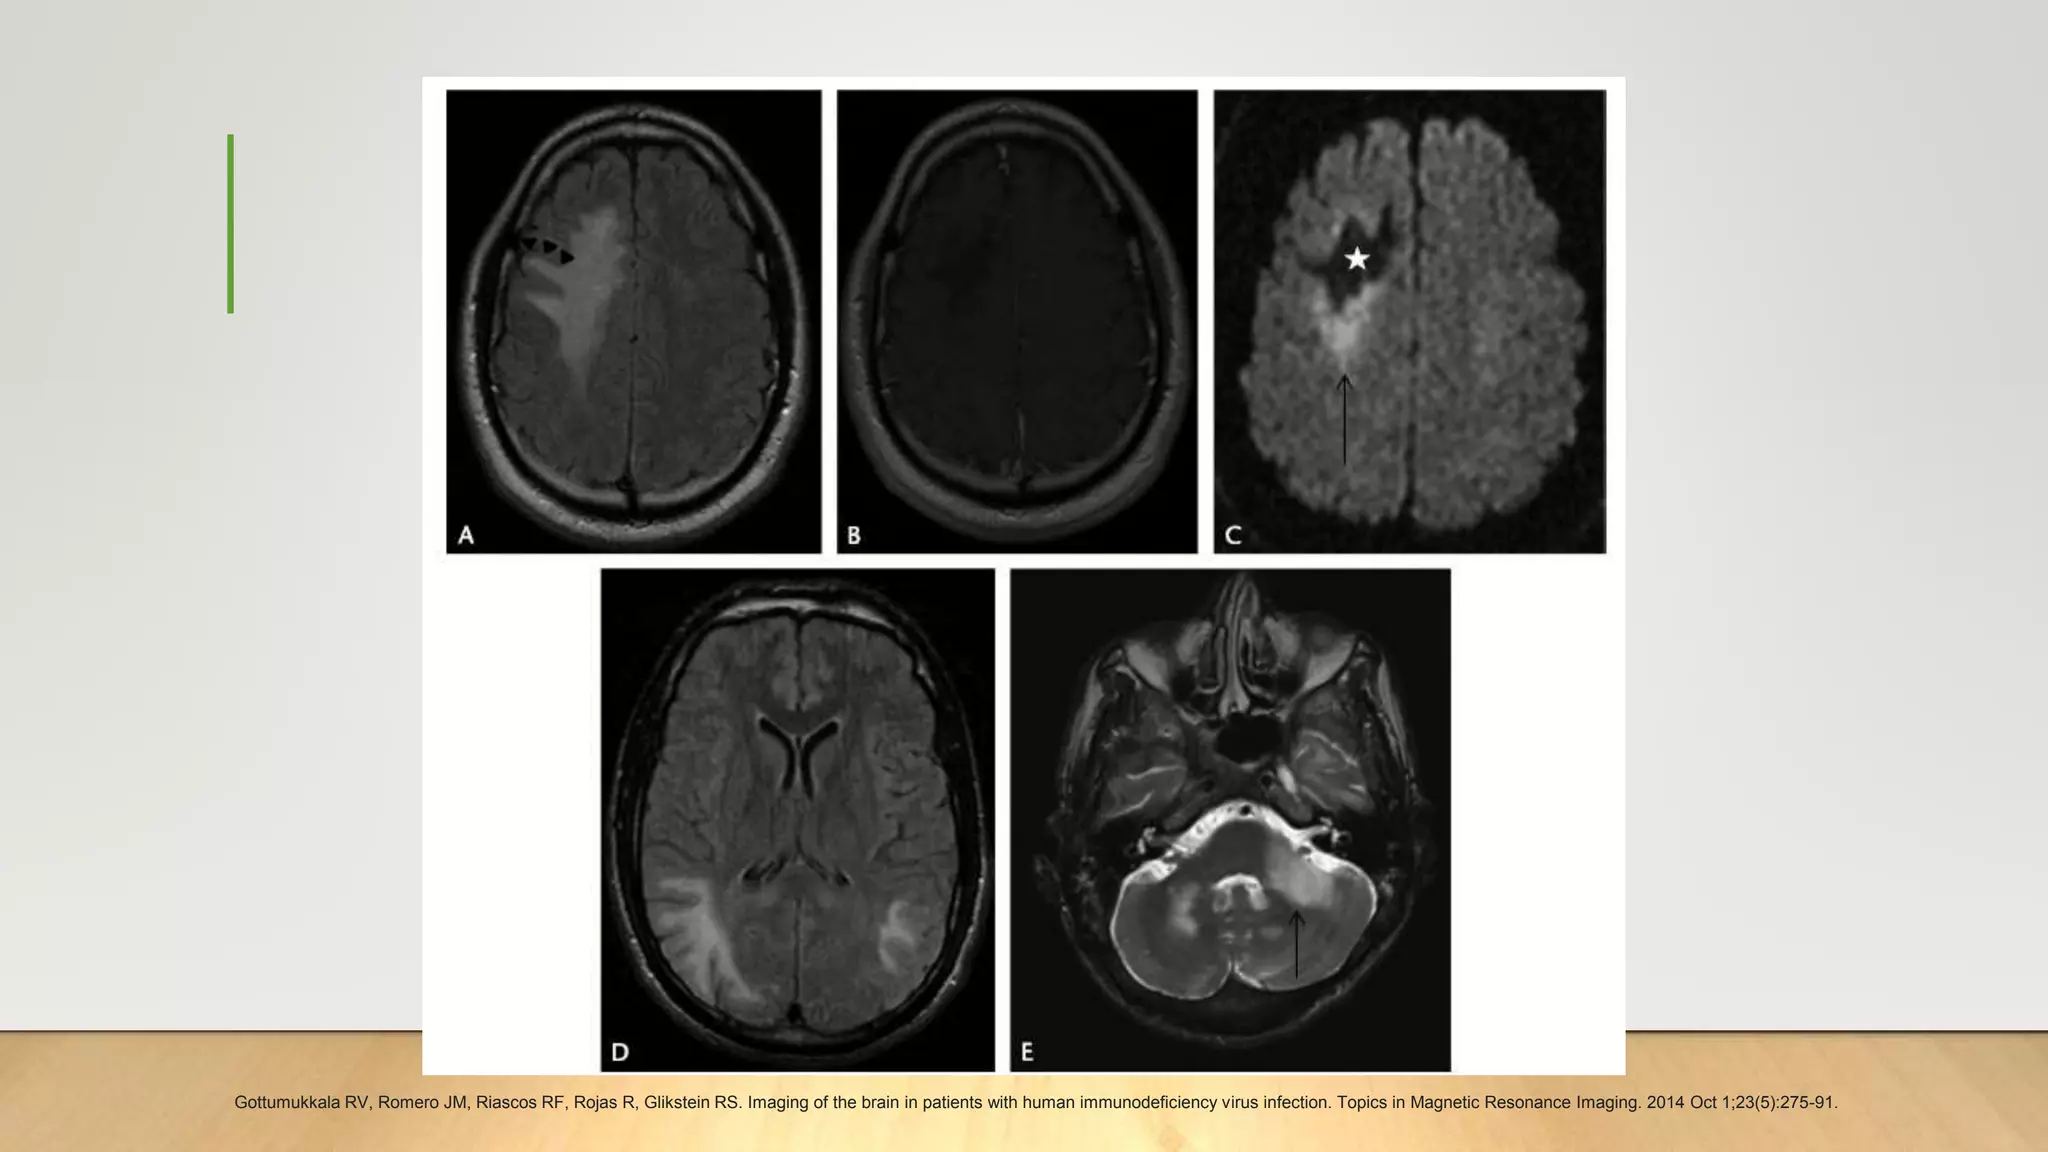

Progressive Multifocal Leukoencephalopathy (MRI)

• PML-IRIS, lesions may cause clinically significant mass effect with or without

heterogeneous enhancement

• Diffusion weighted imaging of PML lesions depicts a central core of low signal with

a corresponding increase in ADC. Surrounding this core is a rim of high DWI signal,

likely representing restricted diffusion from cellular swelling at the more active

leading edges of the lesion

Gottumukkala RV, Romero JM, Riascos RF, Rojas R, Glikstein RS. Imaging of the brain in patients with human immunodeficiency virus infection. Topics in Magnetic Resonance Imaging. 2014 Oct 1;23(5):275-91.

PML - IRIS